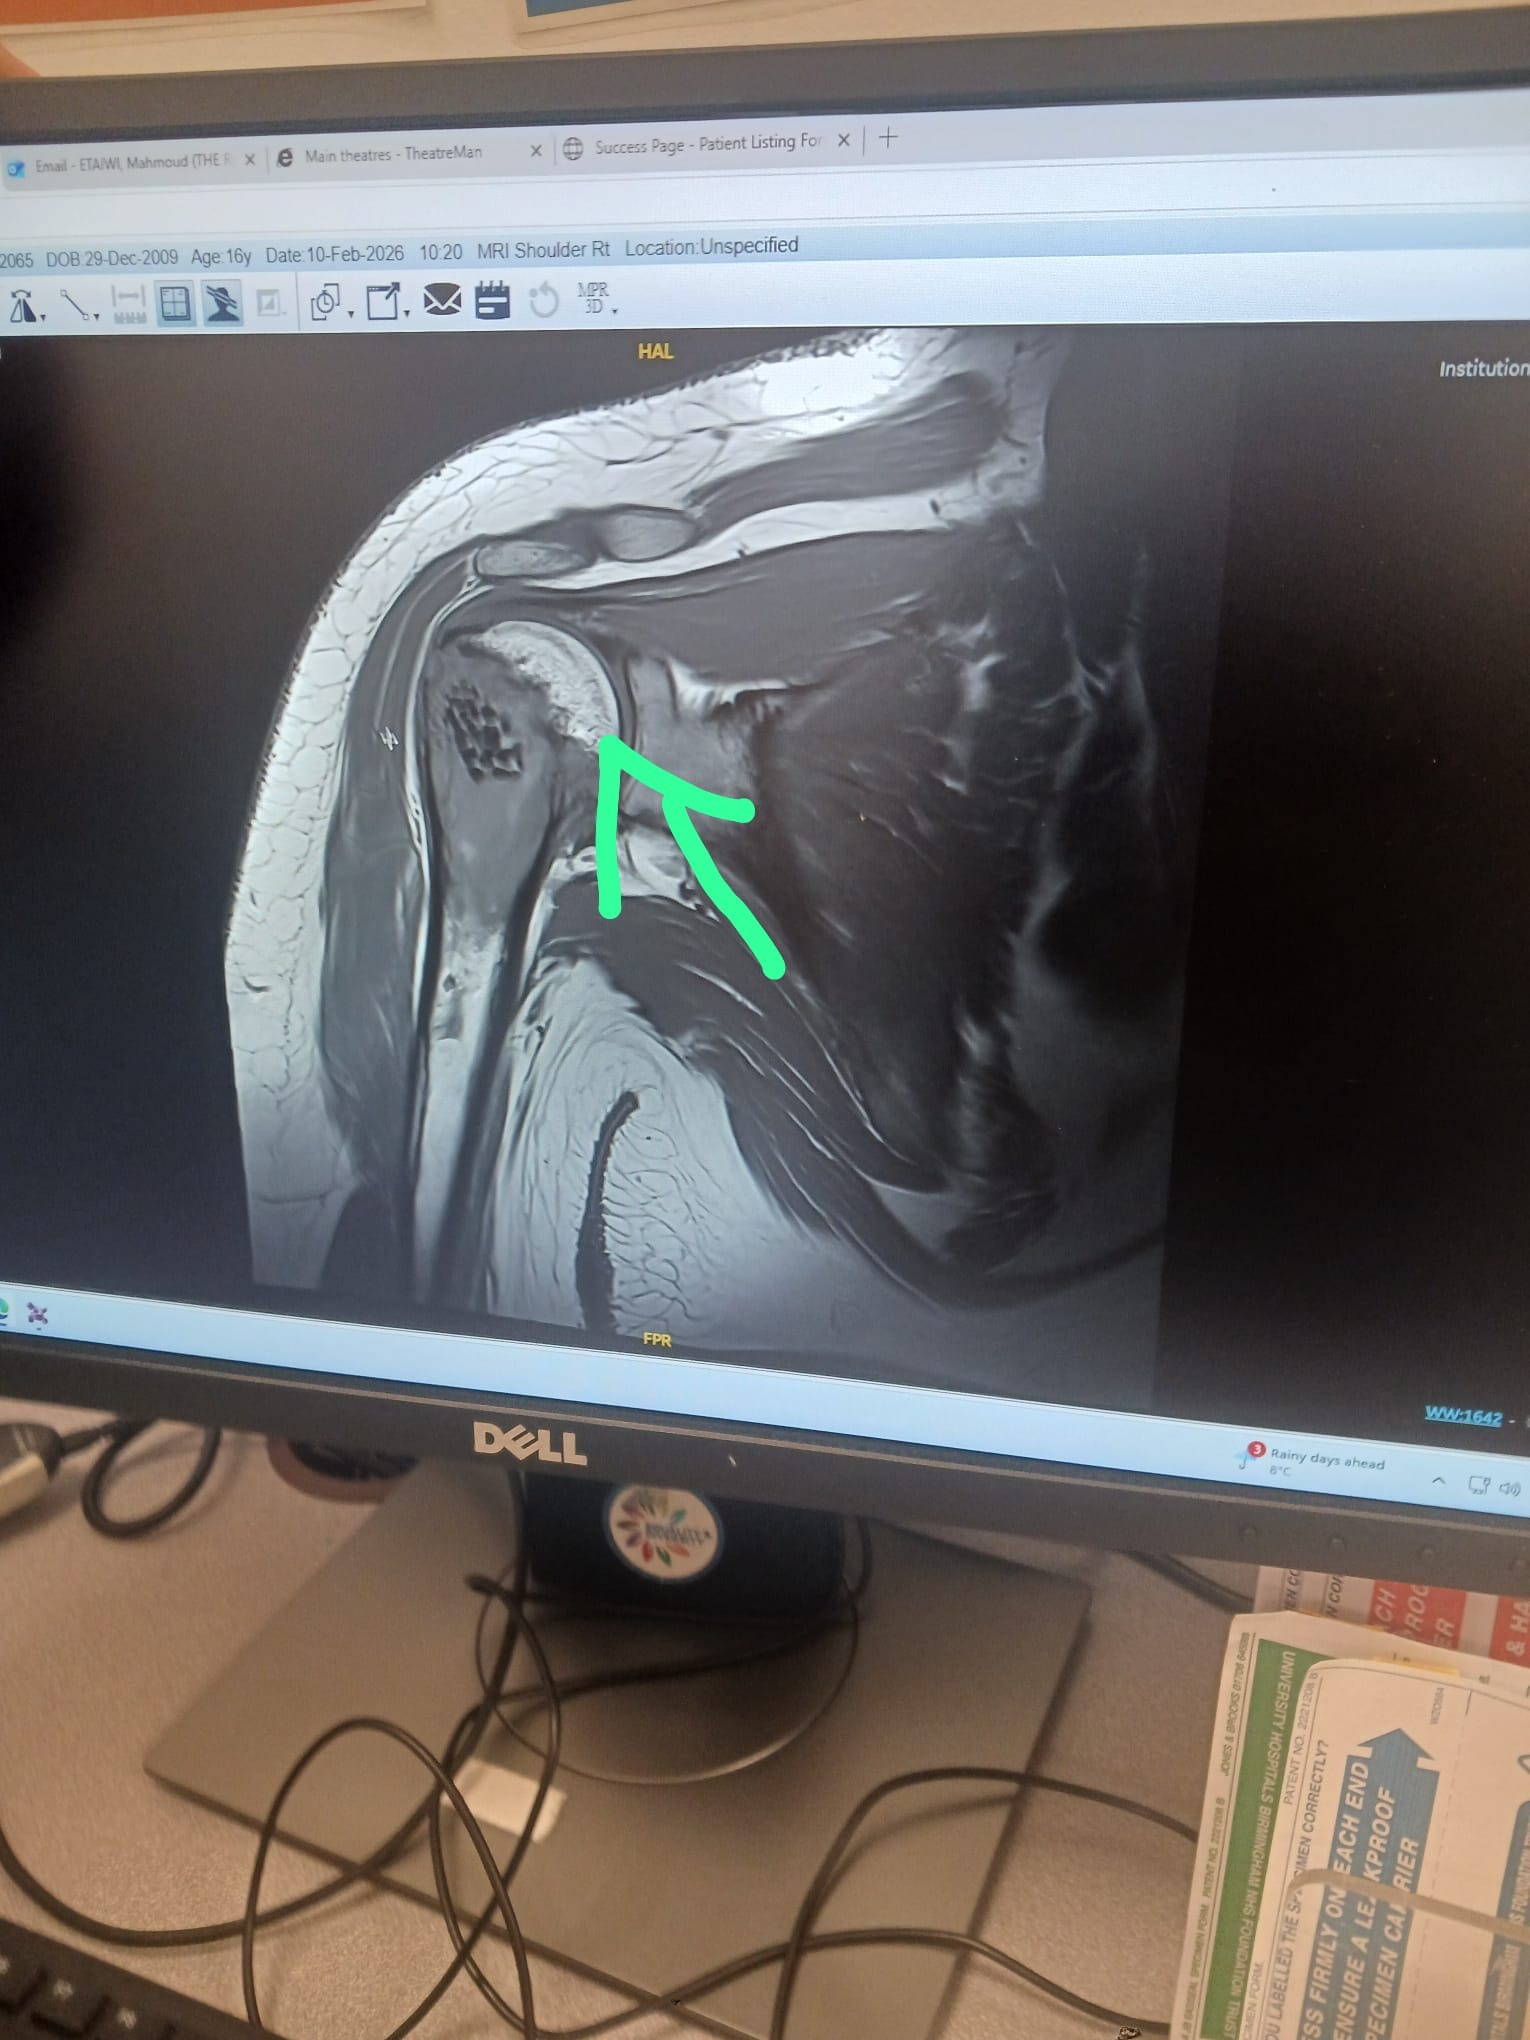

Hello my name is Paul Woolley, proud father of Jack. My partner of 22 years is Rhian and my daughter is called Eryn. Just over a year ago Jack was taken into hospital with septic arthritis in his right shoulder and needed an operation. Little did we know that three stays in hospital later we found out the terrible news that my son had been diagnosed with Ewings Sarcoma a bone cancer. My son Jack has just turned 16 years old and has autism, so this has been very difficult for him and hard to process. Myself and Rhian were heartbroken when we found out and where terrified about what could happen. The doctors have been BRILLIANT and the prognosis is good for Jack and they are hopeful that Jack will make a full recovery. To get to that day Jack will have to endur 36 chemotherapy days over a 17 week period and then surgery to remove the upper right arm bone and then a prosthetic implanted and then possibly more chemotherapy and radiotherapy. We are looking at around 25 weeks give or take. Myself and Rhian both work I'm a support worker of 18 years and Rhian is a dispenser/checker at a local pharmacy. Both of our employers have been great with us but can only help so much. My son needs at least one of us with him all the time and would not be able to cope alone in hospital or at home while he is having his treatment. We are worried about being able to make end's meet while Jack is having his treatment as we will both have to take time off which after a month will be unpaid after using our holidays. It's got us worried to say the least. Any help that you could give would be greatly appreciated and would help us through a very difficult time.